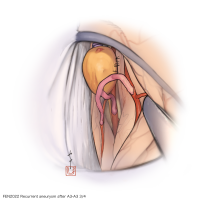

FEN2022シリーズ

術後イラストシリーズ